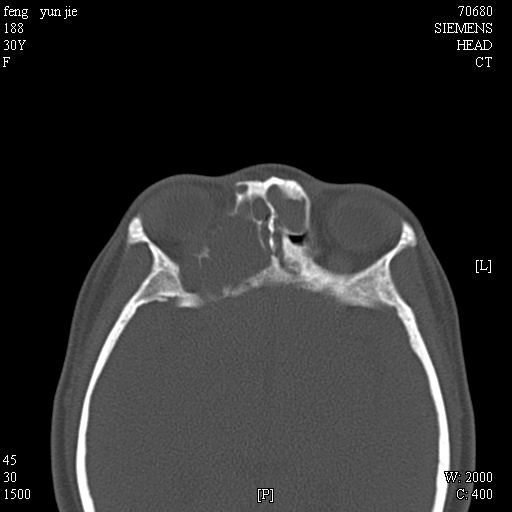

女,37岁,多年前鼻骨骨折过,现在穿刺有炎性分泌物

2、额窦粘液囊肿(右侧水平额窦突入眶内上方)可能性大。

1)左侧鼻骨骨折(陈旧性)。2)双侧额窦及双侧筛窦炎症,伴右侧额筛窦黏液囊肿突入右侧眼眶。

额窦粘液囊肿(右侧水平额窦突入眶内上方)可能性大

是黏液囊状还是淋巴瘤?建议结合穿刺细胞学检查。

考虑额窦粘液囊肿可能性大。